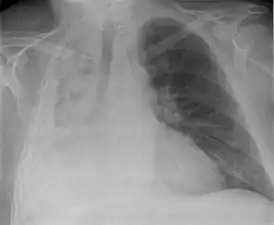

![]() Тотальный ателектаз правого лёгкого (вид спереди) | |

Достаточно часто у больных могут быть симптомы предшествующего поражения лёгких. При остро возникшем значительном ателектазе больные могут ощущать боль в грудной клетке, усиление одышки; при обследовании больного отмечают цианоз, некоторое отставание при дыхании поражённой половины грудной клетки, притупление перкуторного звука в соответствующем участке лёгкого, там же ослабление дыхания и голосового дрожания. Могут быть тахикардия, гипотония, при осложнении ателектаза инфекцией — повышение температуры. Однако часто при постепенном развитии ателектаза и небольших его размерах клинические симптомы могут быть выражены незначительно, и ателектаз диагностируется рентгенологически. При этом прозрачность поражённого участка лёгкого уменьшается, тень его часто имеет треугольную форму с верхушкой, обращённой в сторону корня лёгкого. При большом ателектазе может быть смещение органов средостения в поражённую сторону. Своеобразной формой ателектаза является так называемый синдром средней доли, обусловленный обтурацией крупного бронха увеличенным лимфатическим узлом. Чаще всего этот лимфатический узел оказывается поражённым вследствие перенесённого туберкулёза. Для уточнения причины ателектаза иногда приходится проводить томографию, бронхографию.